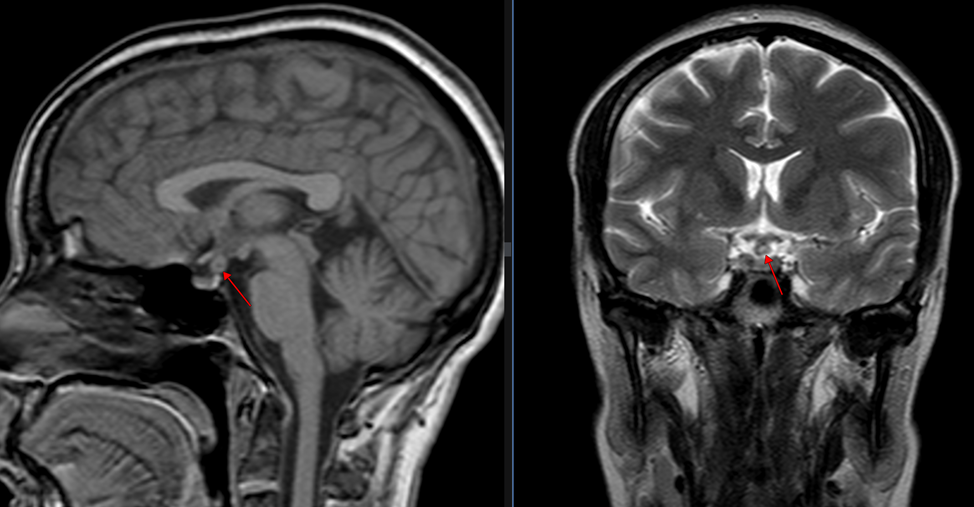

Пациентка В. 36 лет, жалобы на головную боль, головокружение, нарушение менструального цикла.

Рис. 1. Т1-ВИ сагиттальная плоскость, Т2-ВИ корональная плоскость (слева направо).

В области воронки гипофиза утолщение в виде округлой формы образования неоднородной структуры, размером 0.6х0.6х0.7 см. Гипофиз в размерах не увеличен, ткань гипофиза имеет обычный сигнал. Хиазмальная цистерна не изменена. Параселлярные структуры без особенностей. Внутривенное контрастное усиление данной пациентки не проводилось (в связи с полученным отказом).